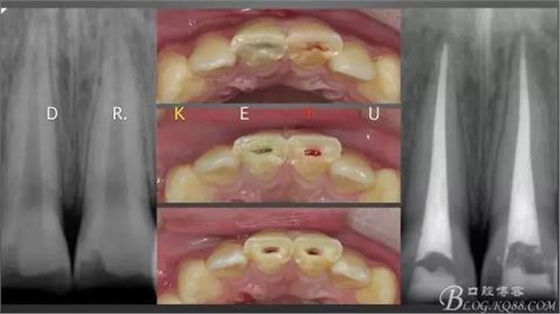

CASE 3—16歲少年外傷后一周來診,RCT后纖維樁及樹脂功能恢復(fù)

一個牙髓壞死,一個活髓,首先一次性根管治療

取研究模型,制作蠟型

復(fù)診于導(dǎo)板下纖維樁及樹脂功能恢復(fù)